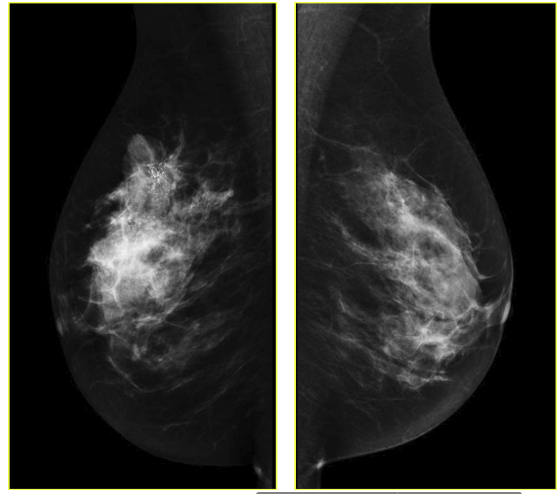

However there is also a novel technique developed in the last few years based on the mammography methodology: contrast-enhanced spectral mammography (CESM). This method, like MRI, is based on imaging of tumor neoangiogenesis by use of a contrast agent [1, 13]. CESM uses a chelated iodine-base x-ray contrast agent, while MRI uses a chelated gadolinium-based paramagnetic agent [14, 15]. Because of high sensitivity of CESM (similar to sensitivity of MRI) this technique maybe comparable with MRI in some cases. CESM, like other diagnostic methods, has some limitations. Benign lesions enhance on CESM, just as they do on MRI. That is, there is no possibility to generate a time-enhancement curve, comparable to that in breast MRI [11, 16]. Just as with mammography, CSEM sensitivity and specificity also varies depending on the age of the examined group and number. Sensitivity and specificity varies from 92.7% to 100% and 41% to 69.7%, respectively [11]. Exemplary CSEM images for CC and MLO views are shown in Fig. 2.